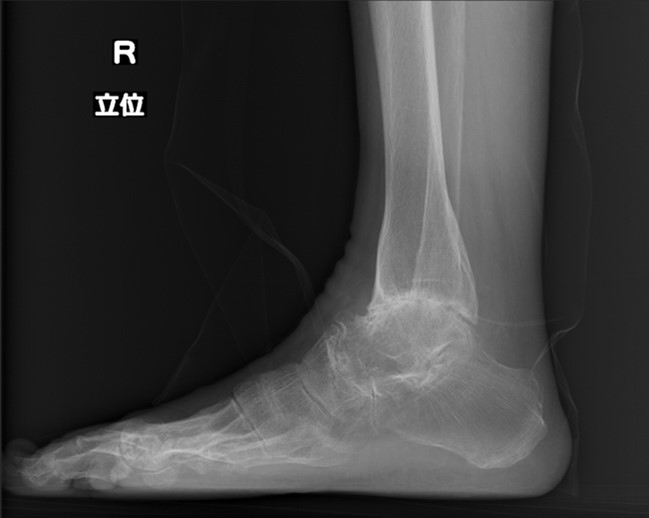

7.足関節の破壊に対する人工足関節置換術

最近はtrabecular metalという構造を持った人工足関節で骨セメントを使用しなくても手術ができるケースが増えています。